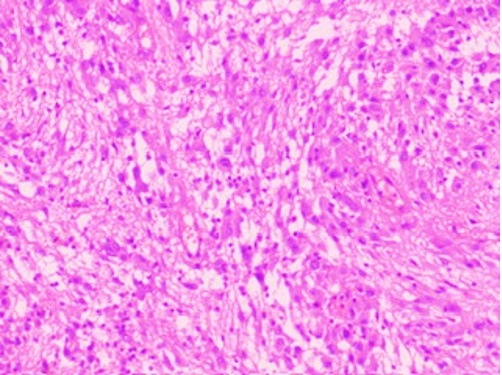

Figs 1 and 2 from a mass in the right hypochondriac region.

Fig 2 : Giemsa x 400